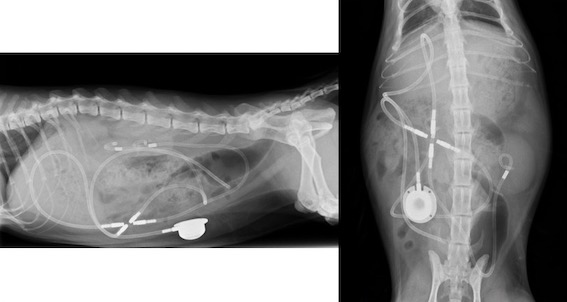

レントゲン検査画像です。

今回の症例は、左側の腎盂内に複数個の結石があり、その1つが近位尿管に閉塞していました。同時に膀胱結石も認められました。

腎数値も上昇しており(尿素窒素102mg/dl、クレアチニン7.91mg/dl)、1日間点滴治療を行いましたが、改善が認められなかったため、今回はSUBシステムの設置を行うことになりました。

手術後のSUBシステムの位置関係はこのようになります。